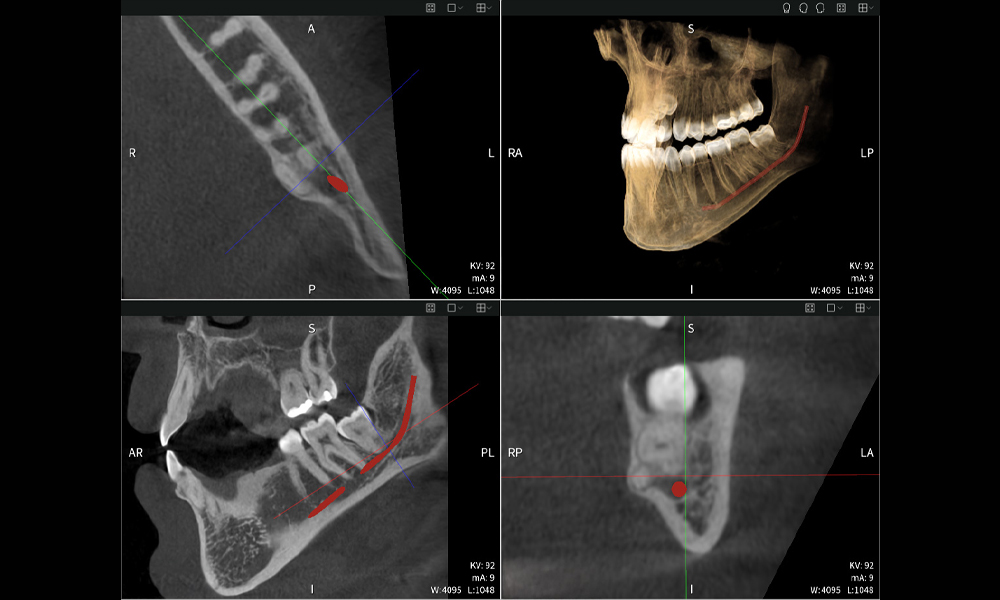

Figura b: Resultados de imagen de Seethrough Max, sobre un fondo negro.

Figura b

Las figuras b–d muestran varias vistas de una reconstrucción 3D de la mandíbula, proporcionando una visión general completa de la anatomía mandibular, la posición de los nervios en relación con los dientes y permitiendo evaluar la simetría y alineación dentaria.